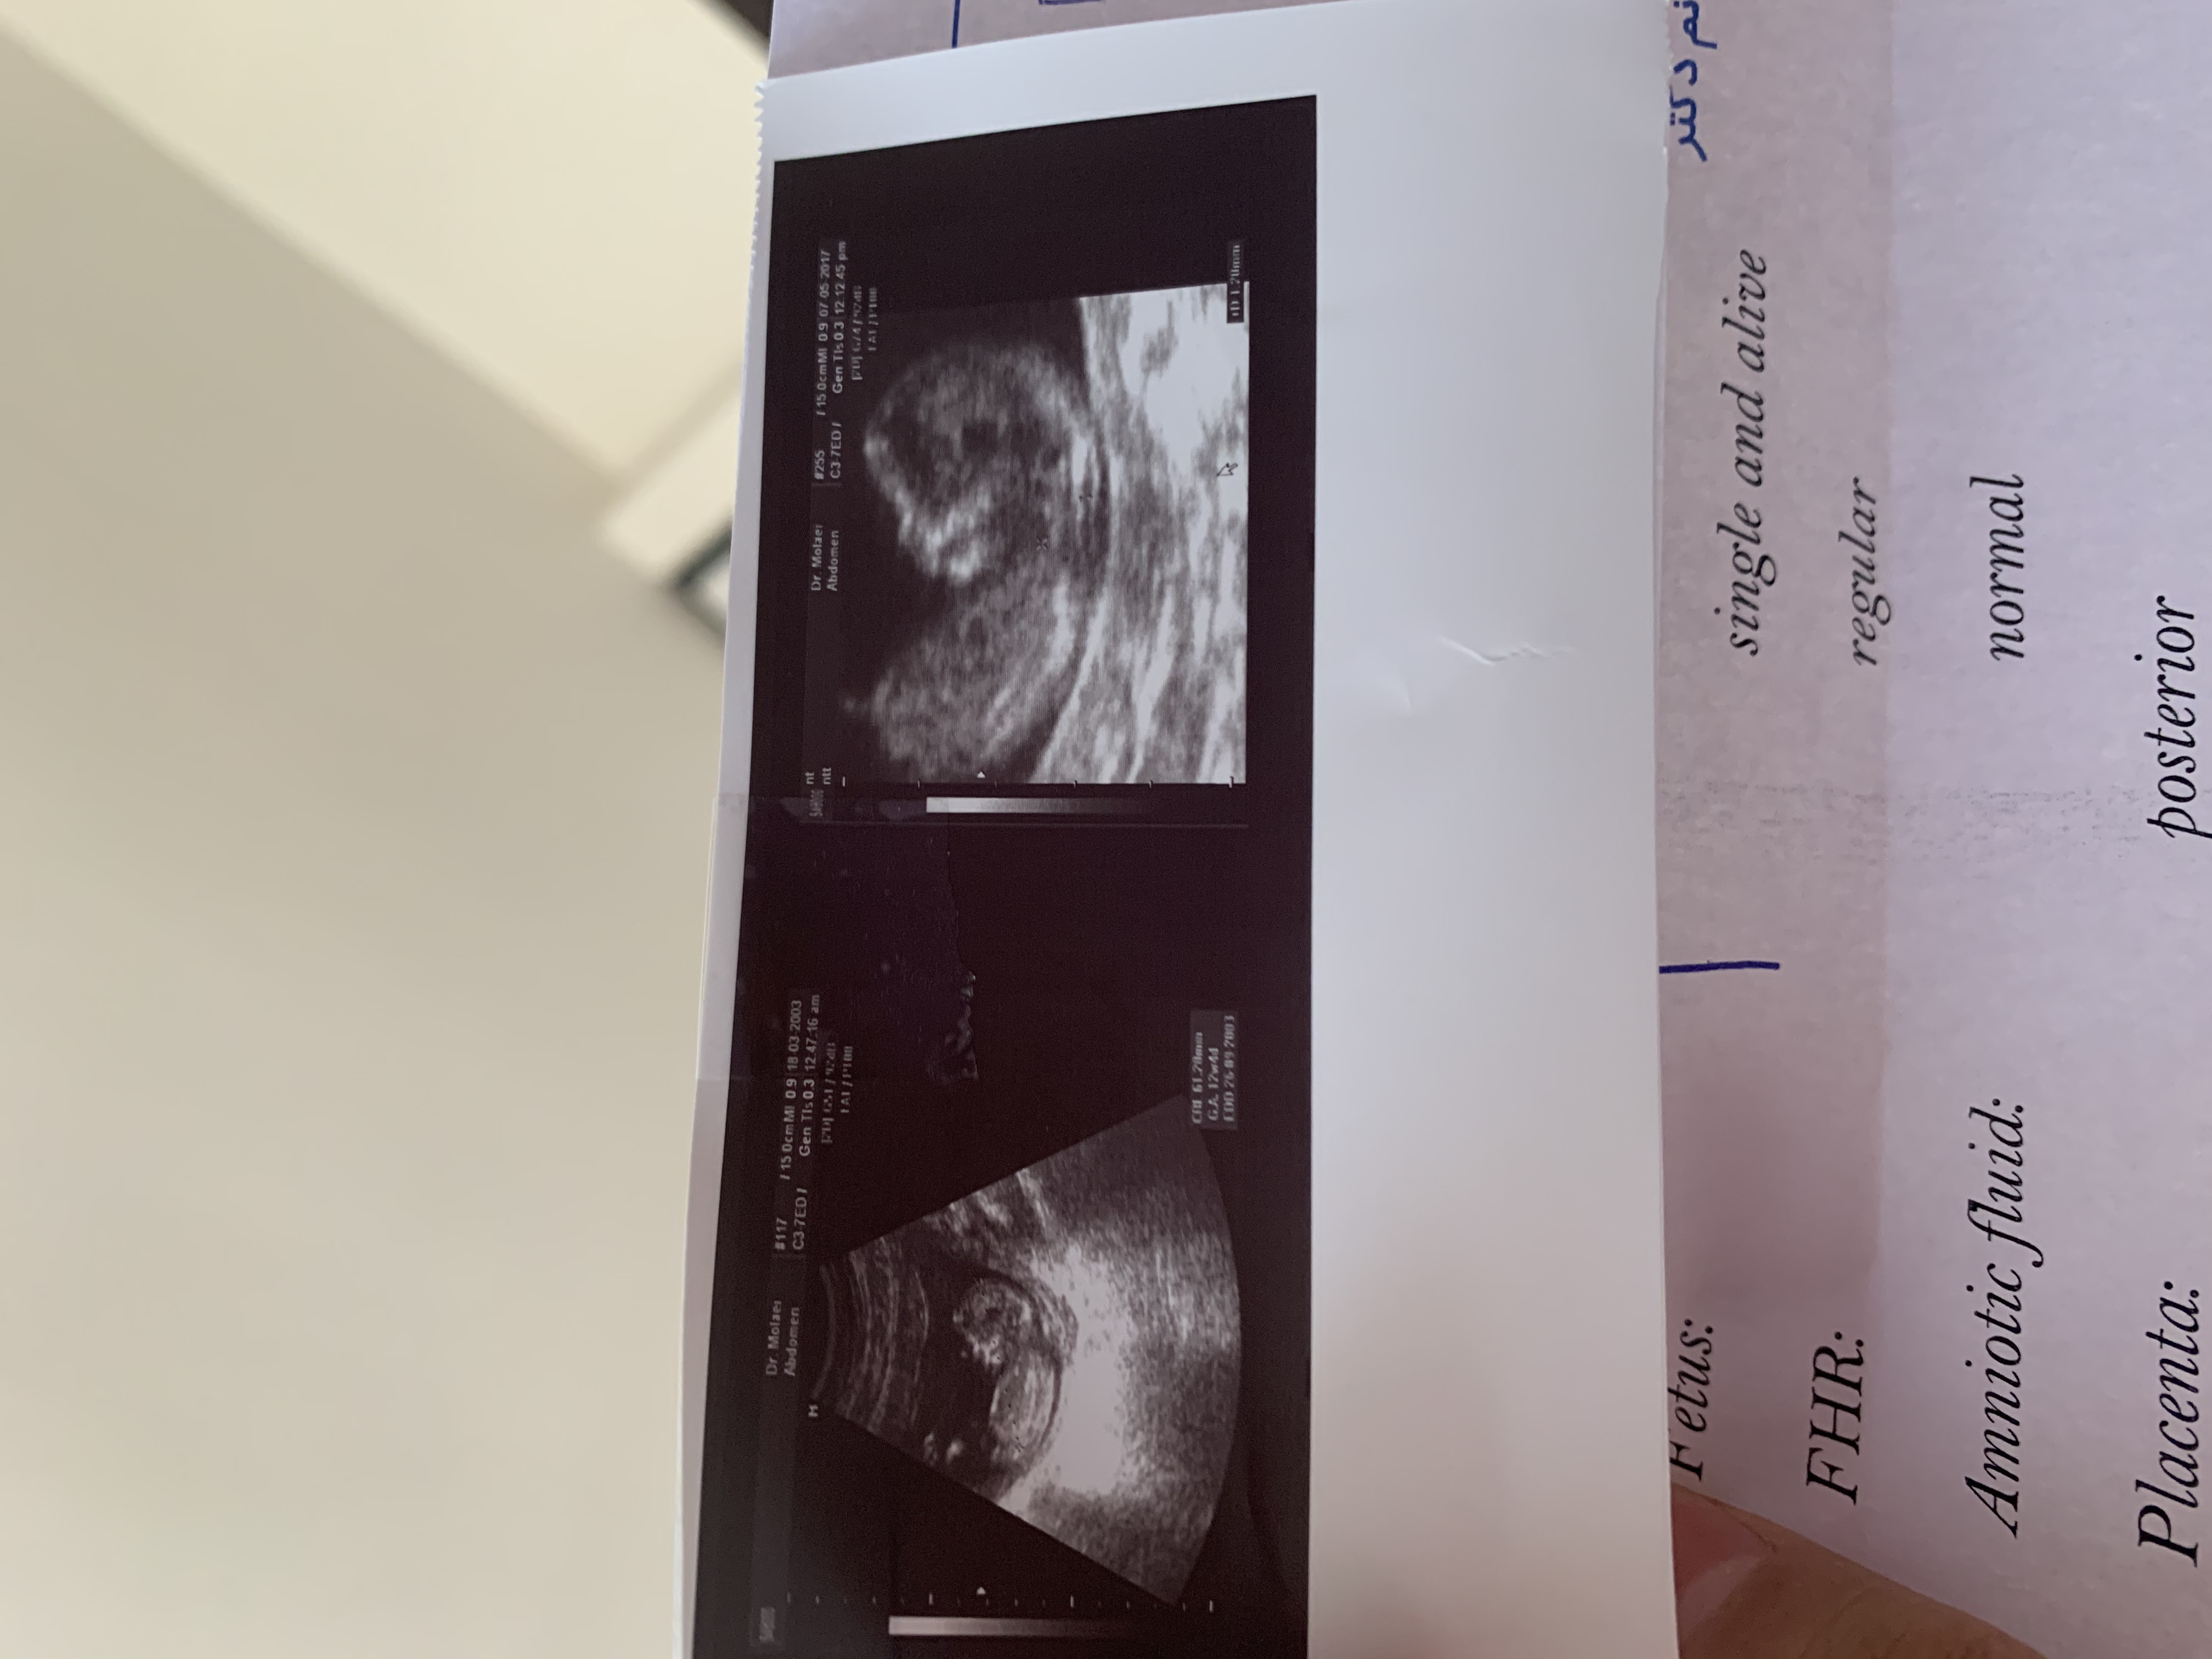

maman_sara72 مدیر استارتر عضویت: 1399/11/27 تعداد پست: 110 اینم عکس سونو کسی میتونه احتمال بده چیه؟؟؟؟؟

ی،کاسه،ذرت،مکزیکی عضویت: 1399/06/11 تعداد پست: 3462 مطمئن هستی به دختر خیلی میخوره تاپیک قبلشم گفته دختره

sarahkh عضویت: 1399/10/09 تعداد پست: 3812 تاپبک قبلشم گفته دختره ها دیدم😐😐...ولی واقعا عکسش به دختر خیلی میخوره. دخترم زندگیمه❤️

maman_sara72 مدیر استارتر عضویت: 1399/11/27 تعداد پست: 110 تو ک دیروز گفتی دختره😬🤔 گفت احتمالا دختر بعد گفت شاید پسر ولی ۶۰ ۷۰ به دختر میخوره

ی،کاسه،ذرت،مکزیکی عضویت: 1399/06/11 تعداد پست: 3462 گفت احتمالا دختر بعد گفت شاید پسر ولی ۶۰ ۷۰ به دختر میخوره پس دختره دیگه